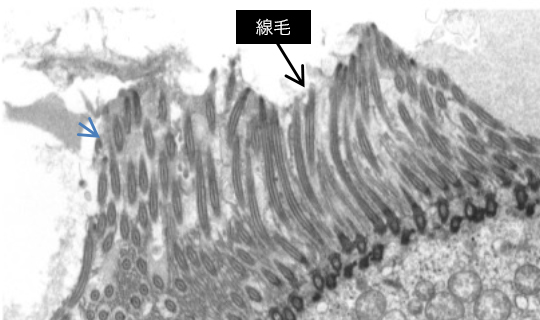

TEM写真例

モルモット鼻腔(fig.1)(fig.2)